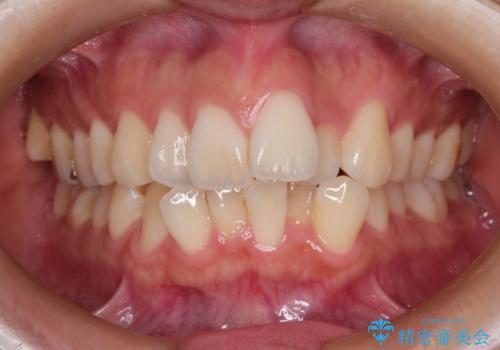

出っ歯を改善した後に真っ白な歯に 矯正歯科治療と審美歯科治療